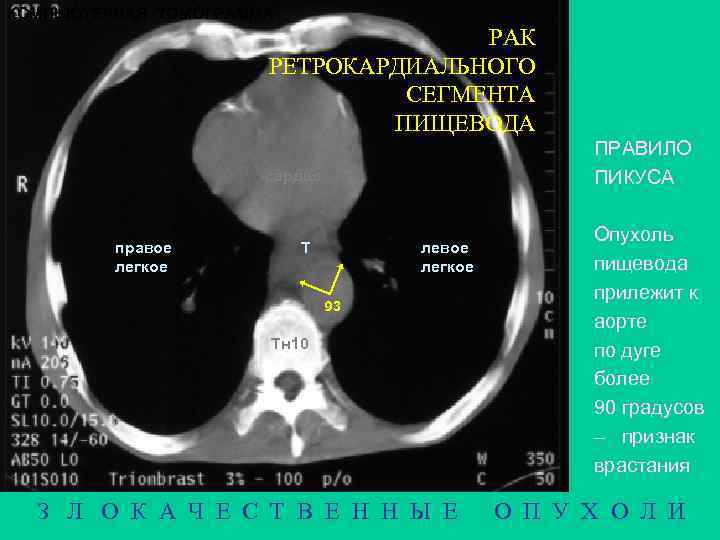

КОМПЬЮТЕРНАЯ ТОМОГРАММА РАК РЕТРОКАРДИАЛЬНОГО СЕГМЕНТА ПИЩЕВОДА ПРАВИЛО ПИКУСА сердце правое легкое Т левое легкое 93 Тн 10 З Л О К А Ч Е С Т В Е Н Н Ы Е Опухоль пищевода прилежит к аорте по дуге более 90 градусов – признак врастания О П У Х О Л И